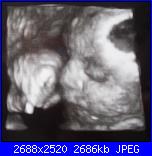

come promesso anche se dopo molto tempo vi dò un piccolo aggiornamento sulla gravidanza ...sono dovuta stare a riposo per un bel pò perchè la piccola voleva già uscire ora per fortuna tutto a posto......ho fatto un controllo un paio di giorni fa pesa già KG1,500 e sono felice di condividere con voi la sua foto ..............alla prossima